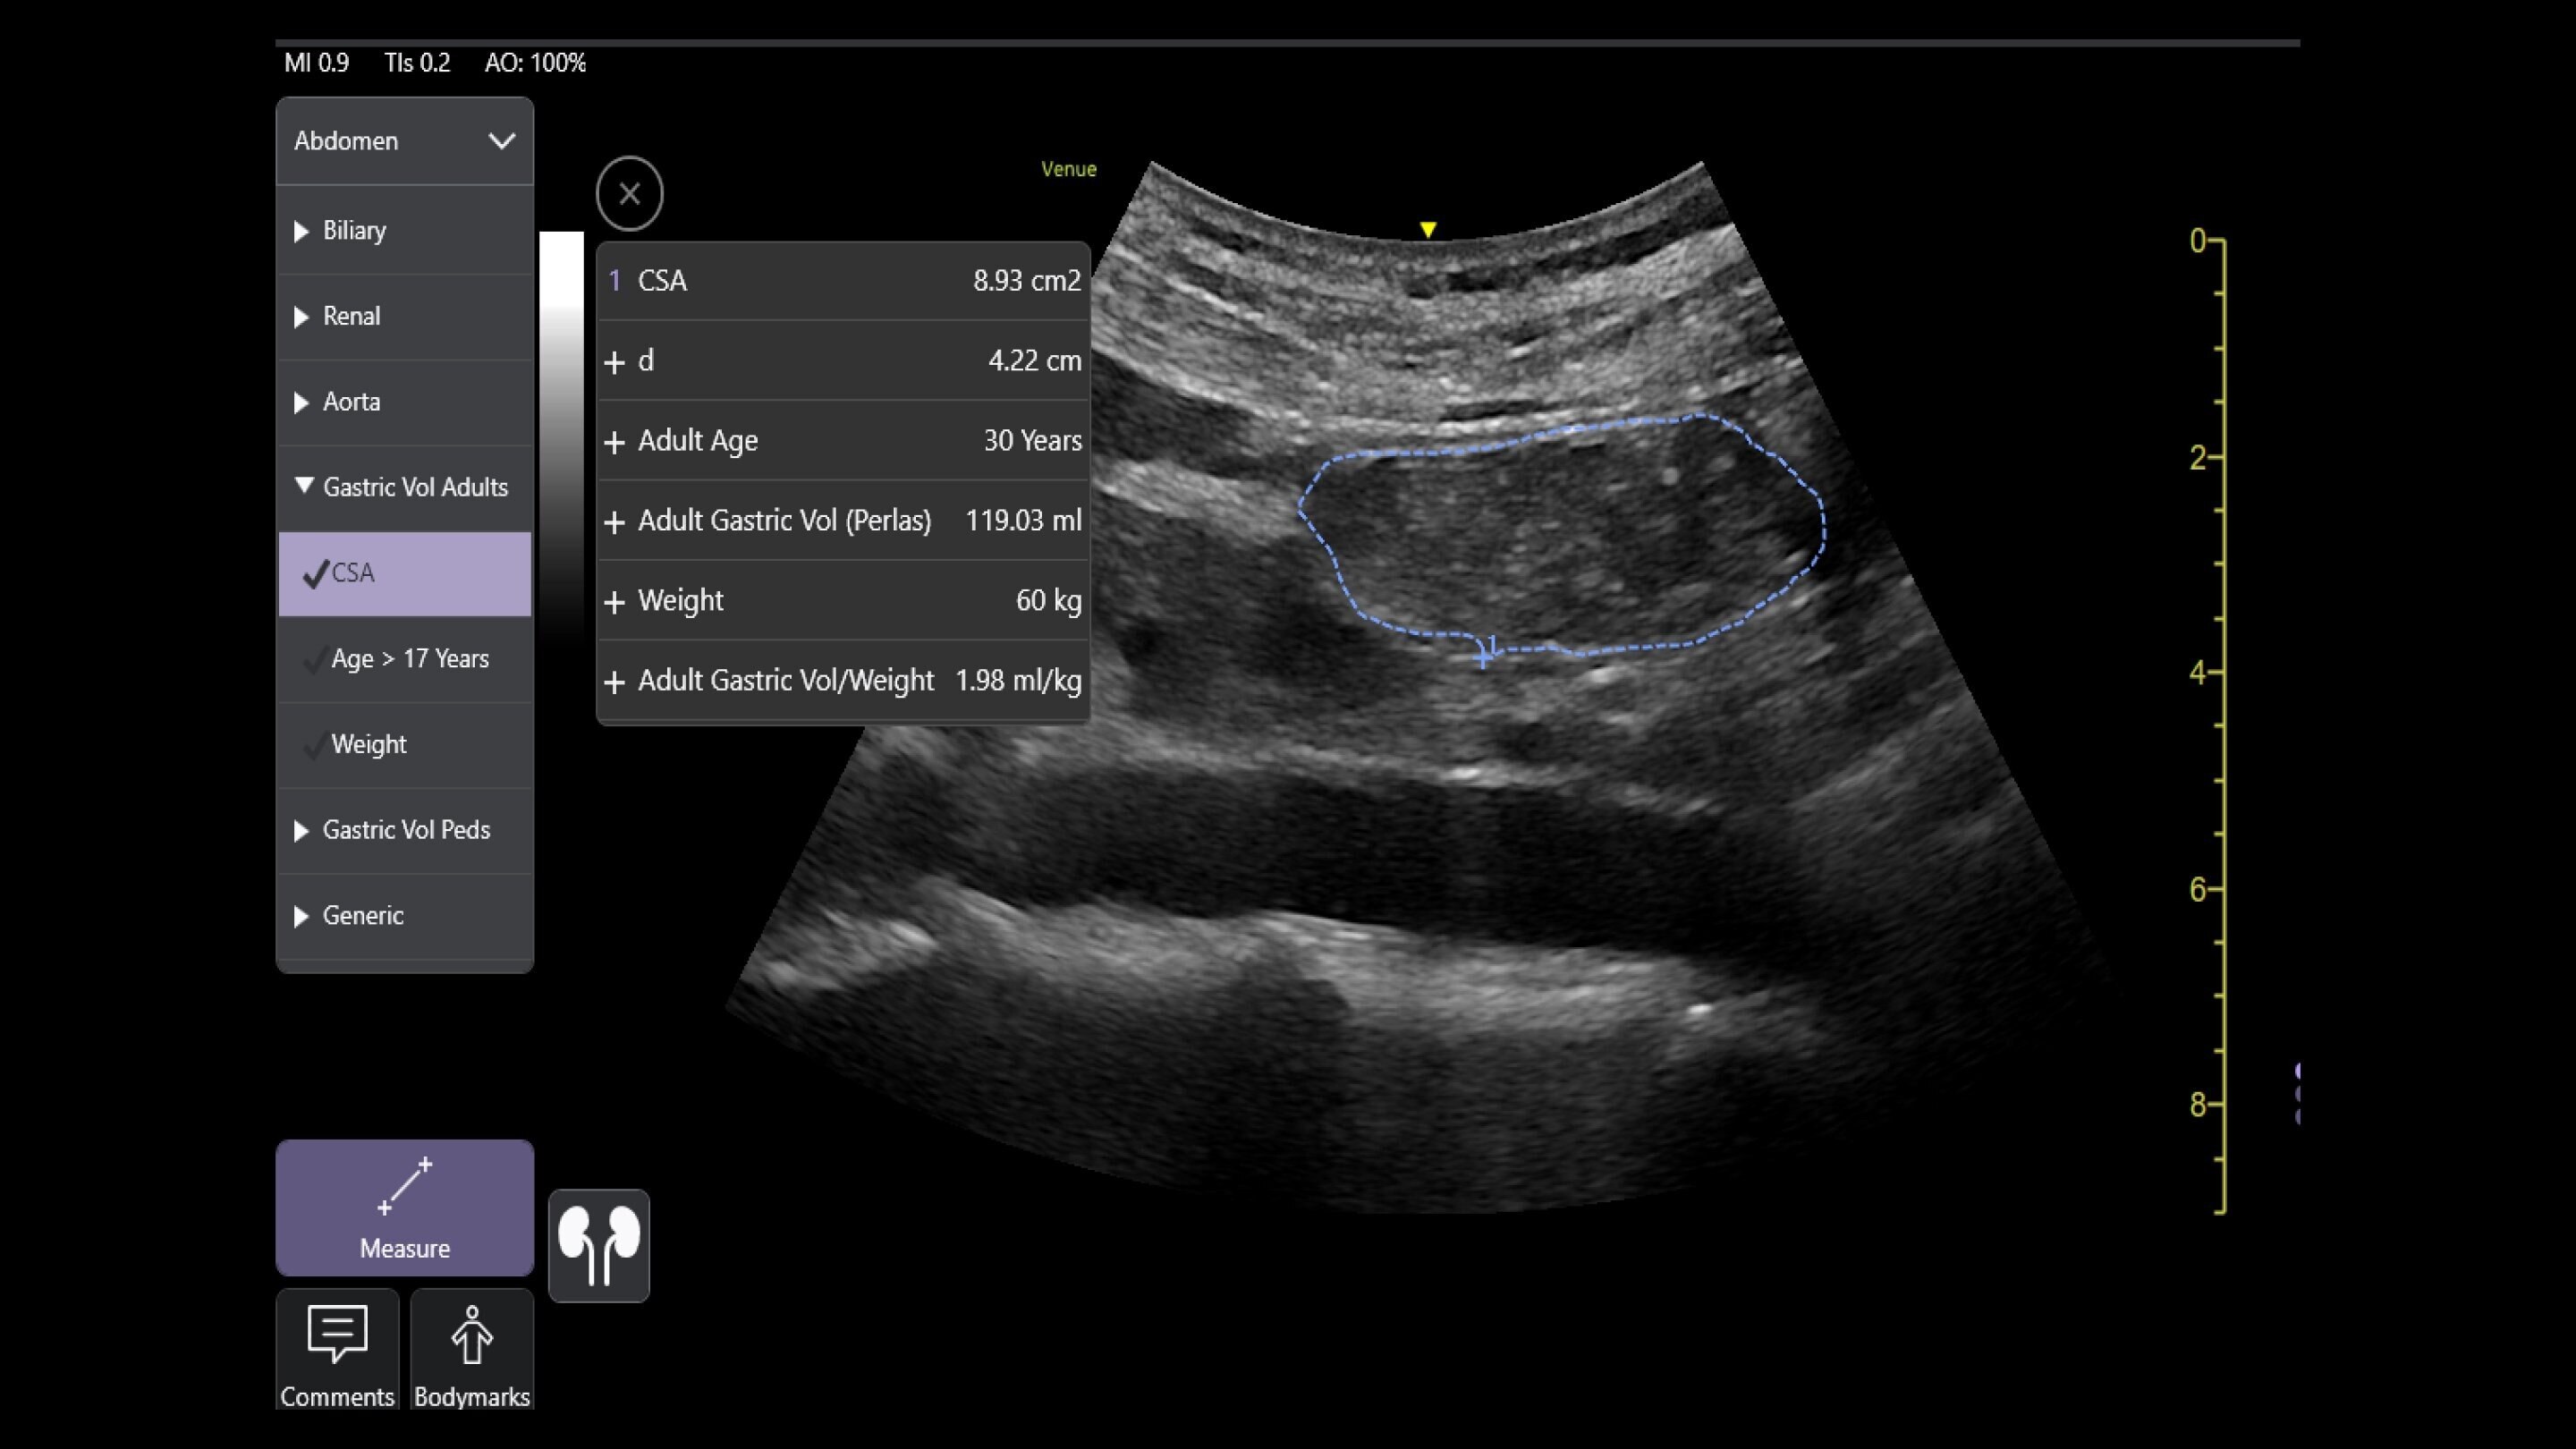

Venue Sprint™ gives you the uncompromised image quality and smart workflow of Venue™ family systems along with the freedom and maximum portability of wireless probes. This all-in-one, entry-level solution combines wireless connectivity with a small, streamlined console. It features Venue family software, to give you access to the AI tools you need, to simplify advanced exams whenever and wherever care is needed.

Now everywhere is point of care*

With the portability and mobility to go anywhere, you can get ahead with Venue Sprint. Take handheld ultrasound to different clinical spaces, sync up and be ready to go. Venue Sprint supports a wide range of environments including: